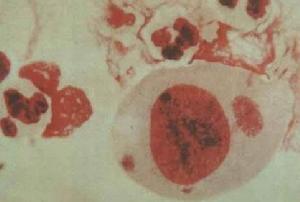

4.尿路真菌感染可表现有尿路刺激症状,尿液一般细菌培养无致病菌生长。但它不同于女性尿道综合征.。它有以下不同之特点:多发于糖尿病肿瘤免疫力低下及长期应用抗生素、激素免疫抑制药及留置导尿管者上行性感染所致。其特征性表现为:尿中排出“真菌球”显微镜下可见真菌孢子和菌丝。 医学百科网 | YxBaike.Com